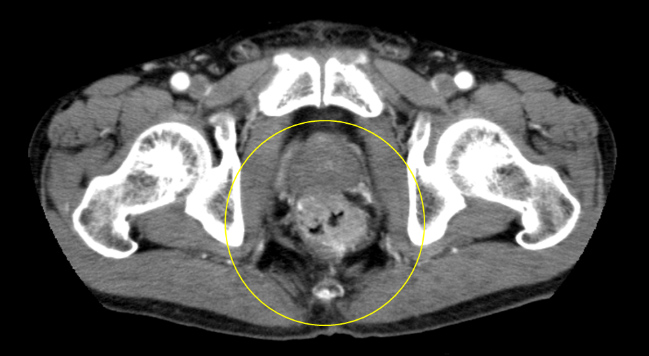

67歳男性。肛門痛を主訴に近医受診し直腸診で直腸癌を疑われ当センターへ紹介となりました。直腸病変は、肛門縁から約1cmに半周性の2型病変を認めた(図1, 2)。他に、S状結腸にも全周性の病変を認めました(図3)。腹腔鏡下に腹会陰式直腸切断術と両側側方リンパ節郭清を施行しました(図4)。

図2 造影CT

S状結腸・直腸の病変を写したCTコロノグラフィー画像

図3 CTコロノグラフィー